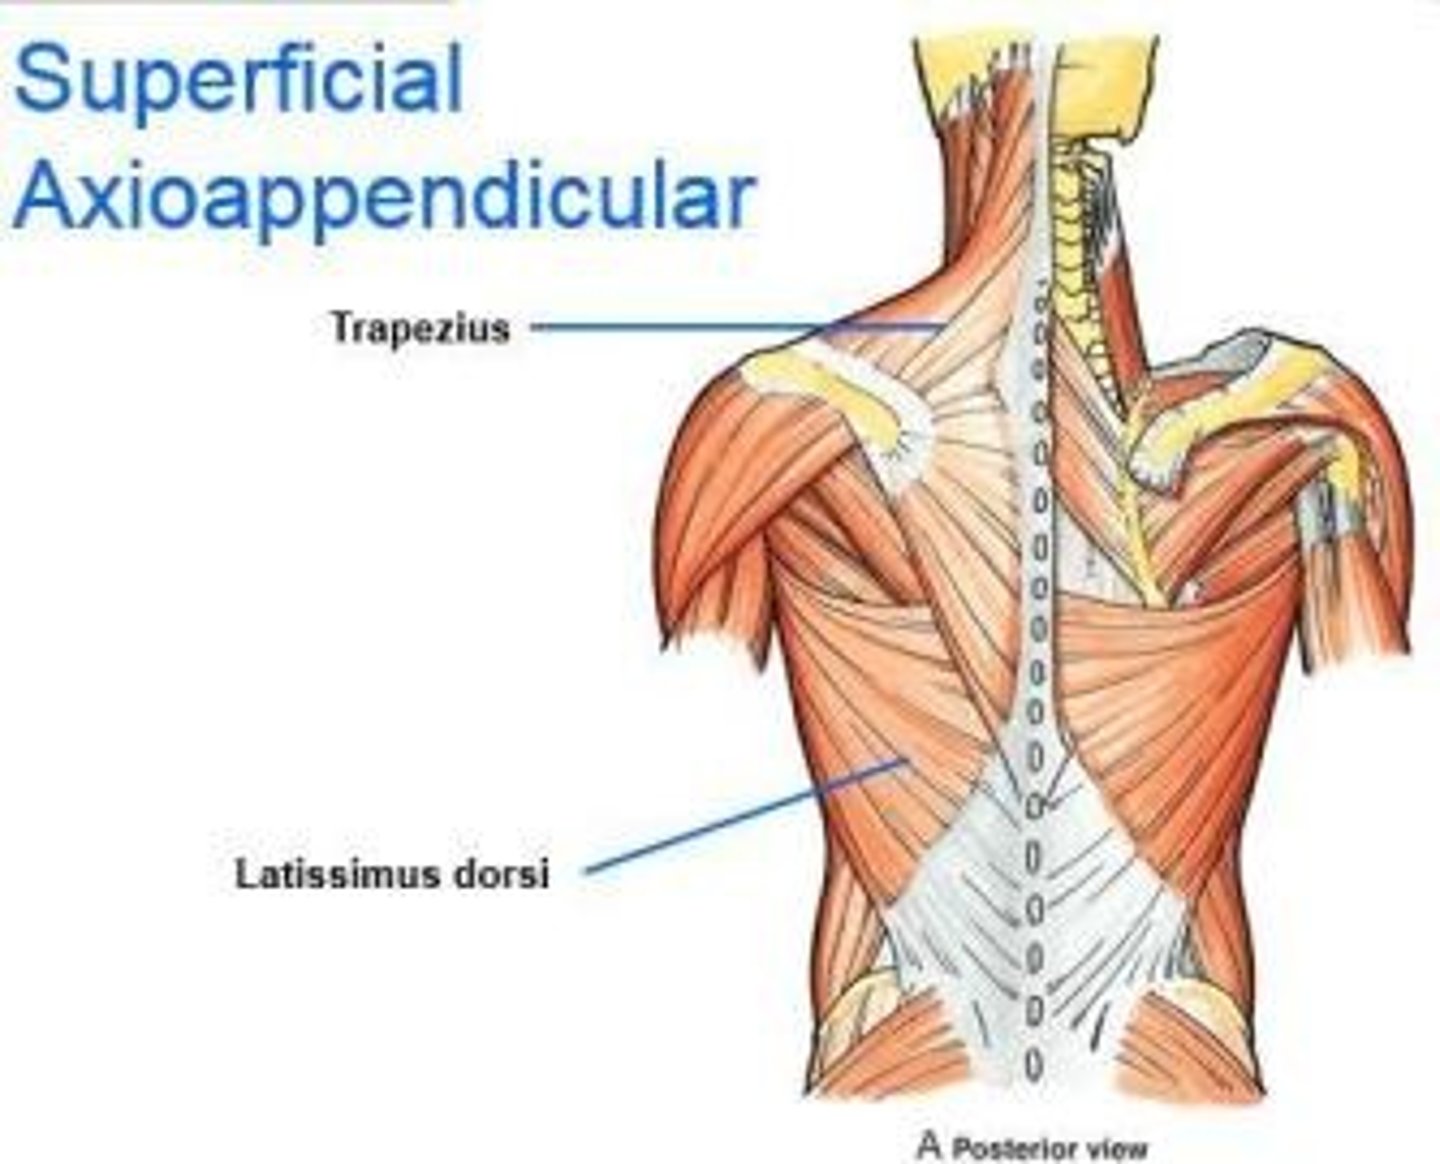

(Posterior axioappendicular and scapulohumeral muscles:) Superficial posterior axioappendicular muscles (extrinsic shoulder)

Trapezius and Latissimus dorsi

(Superficial posterior axioappendicular muscles (extrinsic shoulder):) Trapezius

-Elevates, depresses, and retracts scapula

-Accessory nerve (CN XI)

(Superficial posterior axioappendicular muscles (extrinsic shoulder):) Latissimus dorsi

-Extends, adducts, and medially rotates humerus

-Thoracodorsal n. (C6 - C8)